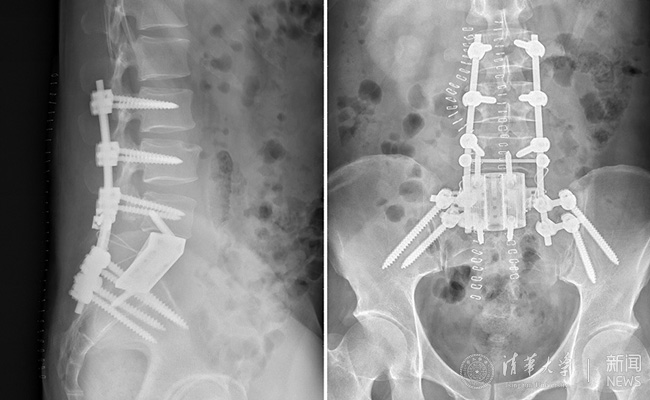

患者术后的骨科照片。

手术在新的一天的凌晨2点结束,术中,跟台护士更换了3批。前后路的转换,患者翻身2次,手术历时10余个小时,生命体征未出现波动。患者在ICU病房几小时后即拔管苏醒。术后的患者如厕正常,并已下地活动,复查X光片,内固定位置良好,假体完全贴合。